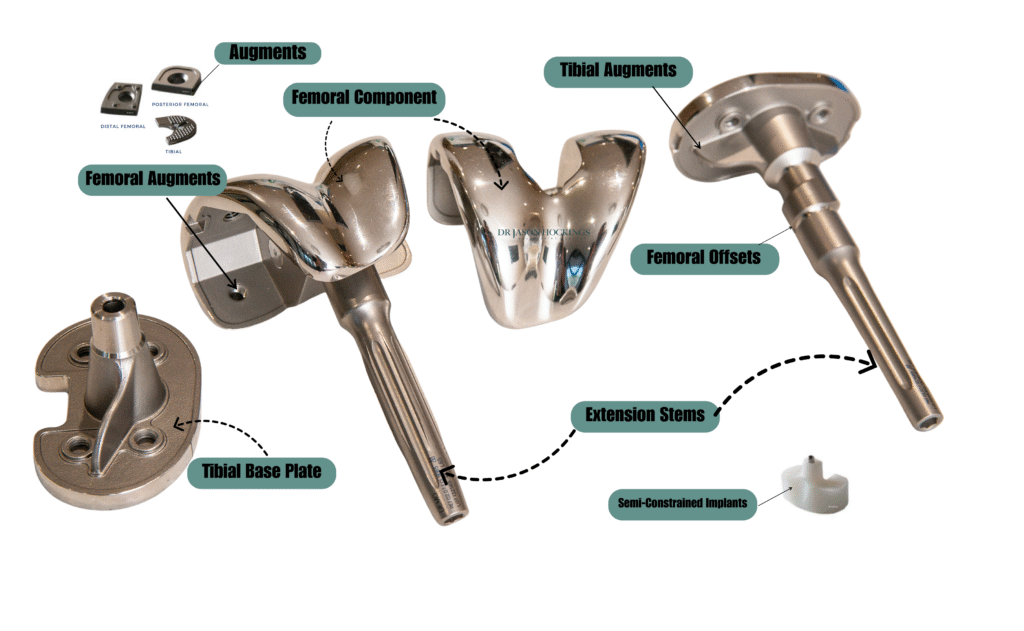

Modern implants & revision knee replacement

Revision knee replacement surgery often involves more than simply exchanging old components for new ones. Over time, changes in bone quality, soft tissues, or ligament support may make standard implants inadequate. Modern revision implant systems are specially designed to address these complexities, offering improved support, alignment correction, and durability.

Whereas a primary knee replacement typically uses standard-sized components, revision implants come in a broader range of configurations to account for bone loss, ligament damage, or joint instability. Dr Hockings uses advanced revision implant systems tailored to your anatomy, surgical history, and functional needs.

Common components used in revision knee replacement include:

- Femoral component: Designed for strength and longevity, often made from cobalt-chromium or titanium alloys.

- Tibial baseplate and insert: The baseplate forms a stable platform, while the polyethylene insert allows smooth joint movement. Inserts may be thicker or more constrained to improve alignment and stability.

- Resurfaced patella: Helps restore a stable interface between the kneecap and femur.

- Extension or intramedullary stems: Long stems that anchor the implant deeper into the bone canal, improving stability in cases with poor bone quality or previous loosening.

- Constrained or hinged implants: Provide greater mechanical stability when ligaments no longer provide adequate support. These restrict excess motion and help maintain joint alignment.

- Augments and wedges: Used to rebuild areas of bone loss, especially around the femur or tibia, to restore the joint’s structure.

- Metaphyseal cones or sleeves: These specialised components fill large bone voids and provide a solid foundation for fixation.

- Tibial and femoral offsets: Allow for precise positioning of components, reducing the risk of overhang or soft tissue impingement.

- Bone grafts: Either from the patient or a donor, grafts can restore lost bone and support the new implant when large deficiencies are present.

Dr Hockings is experienced in selecting and positioning these components based on detailed imaging and preoperative planning. Every revision case is different, and his tailored approach ensures that the most appropriate combination of implants is used to restore comfort, stability, and joint function as effectively as possible.